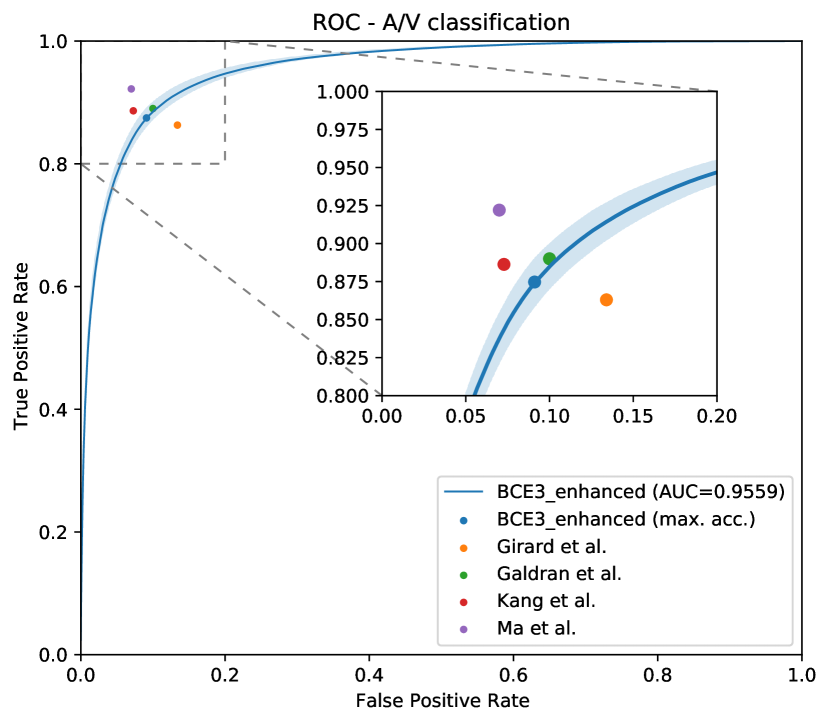

In Figure 8, the mean ROC and PR curves in RITE-test for the networks that were trained using the BCE3 and CE4 losses with and without image preprocessing (“enhanced” and “original”, respectively) are depicted.

Complementing the segmentation results, Figure 10 depicts the ROC and PR curves of the different approaches for the A/V classification in the RITE-test set. These curves are built considering only the pixels labelled as “vessel” in the ground truth, being “artery” the positive class.

As it can be observed in the vasculature segmentation results of Figures 8 and 9 as well as Table 2, the best performance is achieved by the proposed MS approach using the BCE3 loss, either using the enhanced or the original retinography as input, and regardless of the target class. For each structure of interest, i.e. arteries, veins and vessels, both the AUC-ROC and AUC-PR values are higher with the MS approach than with the traditional CE4 one. Furthermore, AUC-PR and AUC-ROC for vessels are significantly higher for the MS approach than for CE4 (), as well as other statistics like AUC-ROC for arteries () and AUC-ROC por veins ().

Regarding the artery/vein discrimination, although the MS alternatives achieve highly positive results (see Table 3), it cannot be affirmed that they perform better than the traditional alternatives. Considering the variability, the A/V classification results of both approaches are not significantly different. However, for the vessel/background discrimination, the situation is different. In this case, consistently with the higher AUC values for vessels segmentation, the MS approach achieves significantly better results () for both Accuracy and AUC-ROC. As can be seen in Table 3, when training with the original images, the sensitivity values of the MS approach are, on average, more than 2.5% higher than those of the traditional approach. Similarly, when training with the enhanced images, the improvement is about 1%. We focus on sensitivity, at a similar level of specificity, due to the positive class that is “vessel”, and the sensitivity measures the proportion of positives that were correctly identified. Specificity and accuracy, although they are also relevant, are much less sensitive in this scenario, since they take into account the background pixels, much more numerous and easier to classify.

Moreover, the methods in the state of the art report the results for a fixed operating point system, with a varying preference for false positives or false negatives among the works. As this complicates the direct comparison between the state-of-the-art results, we complement the results in Tables 4 and 5 with the ROC curves in Figure 15, for the artery/vein classification and the vascular segmentation tasks. In these graphs, we represent the ROC curves for our proposed system (BCE3 loss and enhanced retinographies as input) along with the point representations of the systems in Tables 4 and 5.

As it can be observed in the comparison results, the proposed approach achieves highly competitive results in both the artery/vein classification and the vascular segmentation tasks. In this regard, it is especially relevant that our approach achieves the best performance in the vascular segmentation task among the works aiming at solving both SSCAV tasks, and even a competitive performance with the state-of-the-art specialized methods. This is particularly relevant since, in a real A/V classification scenario, only the detected vessels would be classified into arteries and veins. Regarding the artery/vein classification of the ground truth vessels, however, the achieved results are slightly below the most recent works [40, 41].